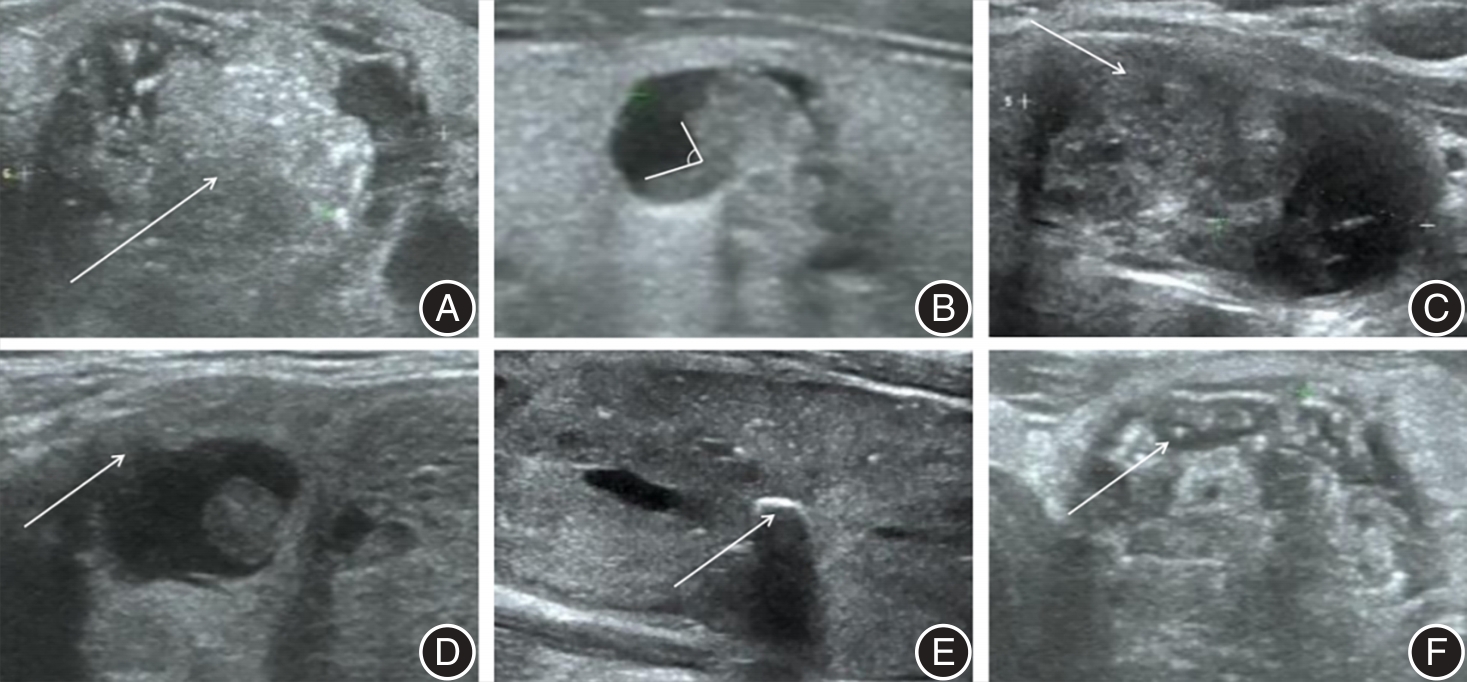

目的 探讨基于超声的迁移学习人工智能模型预测甲状腺囊实性结节(PCTN)恶性概率的可能性。 方法 回顾性分析2021年1月至2023年12月间就诊于山东大学齐鲁医学院威海市立医院并有明确病理结果的PCTN患者246例,以7:3的比例随机分为训练组和测试组。评估PCTN超声图像特征,经过多因素logistic回归分析,得到评估PCTN恶性概率的独立危险因素并计算曲线下面积(AUC)。另一方面,通过Python软件的PyTorch框架对数据进行预处理后,选择5种不同的预训练模型进行迁移学习,具体包括Inception_v3、EfficientNet、VGG19、ResNet50和DenseNet121,计算AUC值并进行比较。 结果 超声图像特征中实性成分> 50%、实性成分与囊性成分呈偏心锐角、病灶边界模糊不清、病灶边界呈毛刺样、蛋壳样钙化和微钙化对于评价PCTN的良恶性差异有统计学意义(P < 0.05),基于以上独立危险因素计算的AUC值为0.843。另外,在5种迁移学习模型中,ResNet50模型诊断效能最高,AUC值为0.903 2。 结论 基于超声的迁移学习人工智能模型优于传统超声图像评价效能,能够准确预测PCTN的性质,从而减少不必要的超声引导下细针穿刺活检。